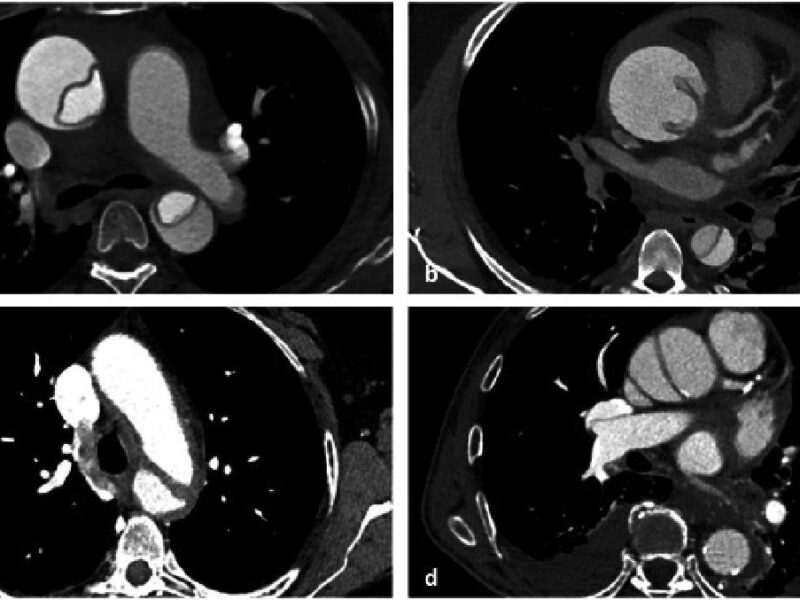

Parce que les cancers peuvent provoquer des pathologies pulmonaires sous-jacentes aux étiologies variées, il peut être délicat pour les radiologues de distinguer ces dernières des manifestations du virus SARS-CoV-2 chez des patients atteints de Covid-19 sur des scanners thoraciques, expliquent les auteurs iraniens d’une étude parue en février dans BMC Medical Imaging [1]. Un défi diagnostique d’autant plus complexe que la littérature sur le sujet fait défaut : « À notre connaissance, il n’y a pas eu d’études suffisantes pour évaluer les effets d’un cancer sous-jacent sur l’apparence de la Covid-19 et son rôle pronostique dans la mortalité au sein de ce groupe spécifique », constatent les chercheurs.

Faezeh Khorasanizadeh et ses confrères ont donc collecté les examens de scanner thoracique de 266 patients avec antécédents de cancer inscrits dans le registre « Covid-19 » de l’hôpital Imam Komeini entre 2020 et 2022. Ils ont inclus dans leur étude